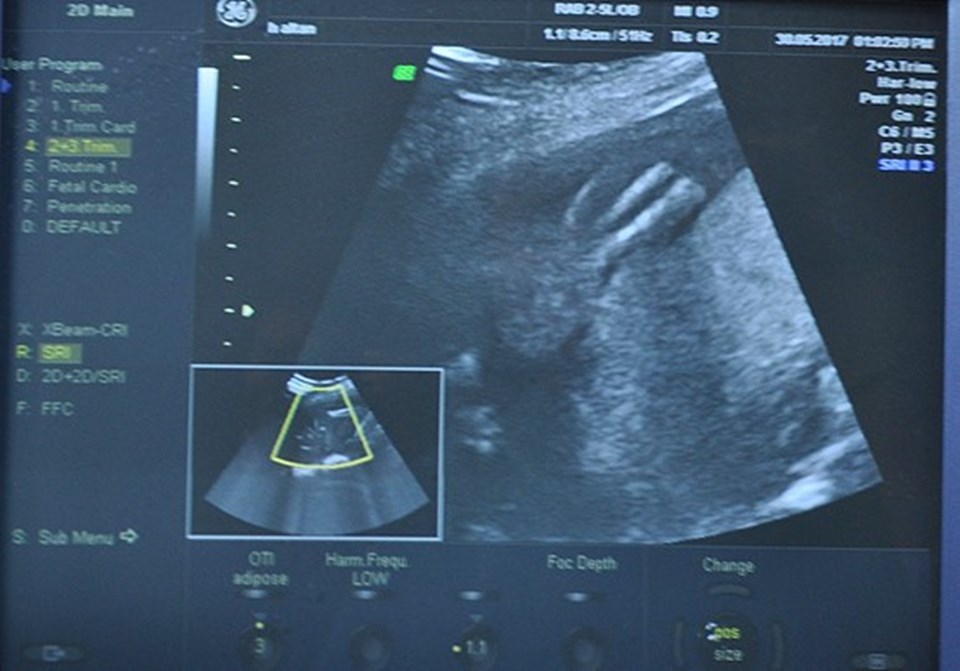

Konya Necmettin Erbakan Üniversitesi Meram Tıp Fakültesi Hastanesine başvuran 5 aylık hamile Hanife Altan'ın (20) kız bebeğine "Amniyotik band sendromu" teşhisi konuldu.

İçinde bulunduğu amniyon sıvısıyla dolu zarın parçasının ayrılarak, sol ayağını sarıp sıktığı görülen bebeğin ayağının tamamen kaybolma ihtimali olduğu tespit edildi.

Meram Tıp Fakültesi Kadın Hastalıkları ve Doğum Ana Bilim Dalı Öğretim Üyesi Prof. Dr. Ali Acar, kan akışı sağlanamadığı ve ayakta gelişim geriliği olduğu için bebeğe anne karnında müdahale etti.

Henüz 300 gramlık bebeğin ayaksız doğmaması için Acar ve ekibi riskli operasyonu başarıyla gerçekleştirdi. Sağlık durumu iyi olan ve doğuma kadar düzenli takip edilecek bebeğin ayaksız doğmasının önüne geçildiği bildirildi.

Prof. Dr. Ali Acar, tetkiklerde zarın parçasının sardığı ayakta kan akışının durduğunu hatta ayak parmağın birinin de iyice küçüldüğünü gördüklerini söyledi.

"Bu şekildeki vakalara direkt tedavi yöntemi yok. Sadece deneysel safhada çalışmalar var. Biz bu operasyonu gerçekleştirilen ender kliniklerden biriyiz. Annenin dokularından geçip rahmine girdik. Çocuğu gördükten sonra kemiğe kadar yaklaşan bandı bulduk. Optik dediğimiz küçük makasla bandı kesip ayağı rahatlattık. Çocuğun damarını, sinirini kesebilir, zarar verebilirdik. Dikkatli şekilde işlemi gerçekleştirdik. Bebeğimizin durumu gayet iyi. Sürekli kontrolümüzde olacak. Elsiz ve ayaksız doğan bebeklere bakıldığında çoğu ya anne karnında tespit edilemiyor ya da müdahale edilemiyor. Operasyonu dünyayla paylaşacağız."